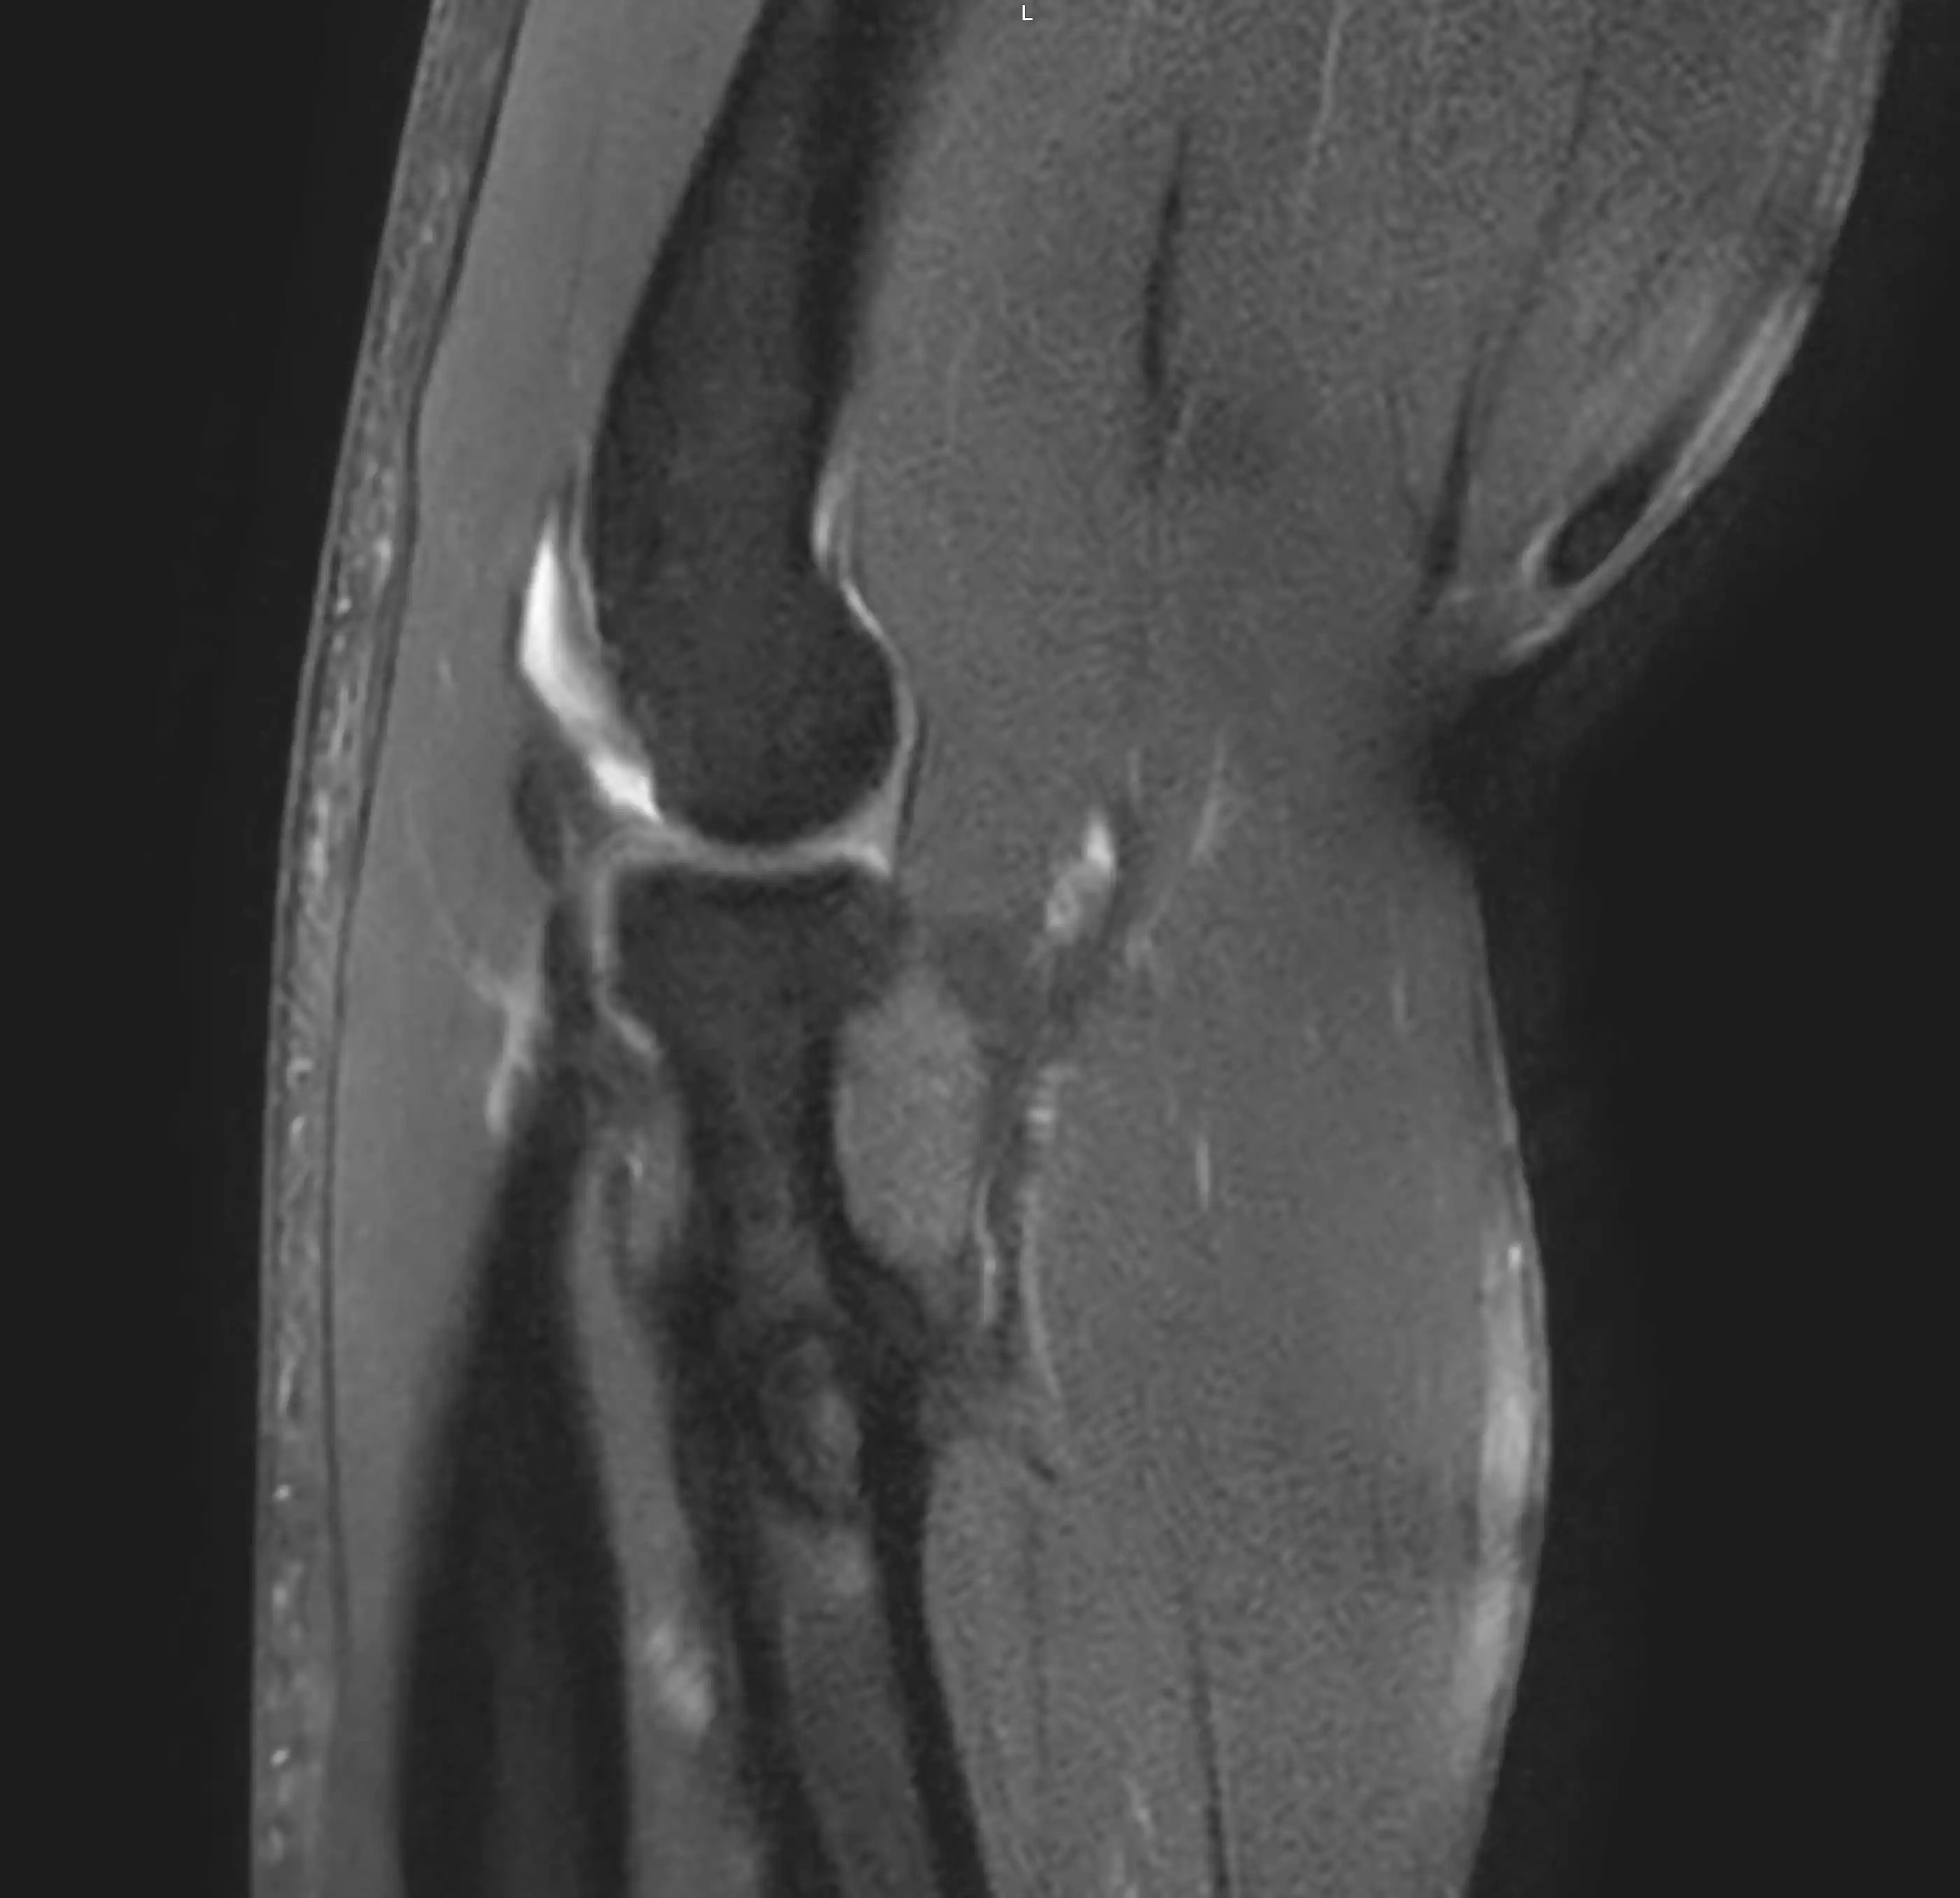

МРТ ліктьового суглобу — це сучасний та високоточний метод обстеження, який дозволяє детально оцінити стан кісток, зв’язок, сухожиль, хрящів, нервів та м’яких тканин у ділянці ліктя.

Магнітно-резонансна томографія допомагає виявити причини болю, обмеження рухливості та інших патологічних змін у ліктьовому суглобі без використання рентгенівського випромінювання.

Що показує МРТ ліктьового суглобу

МРТ дозволяє виявити:

- пошкодження зв’язок і сухожиль

- розриви м’язів

- запальні процеси

- артроз ліктьового суглобу

- травматичні ушкодження

- патології хрящової тканини

- новоутворення

- ураження нервових структур